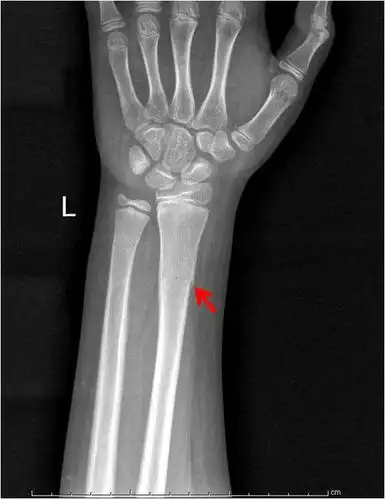

小儿骨折微创手术治疗

左腿ap外侧骨折x线片.